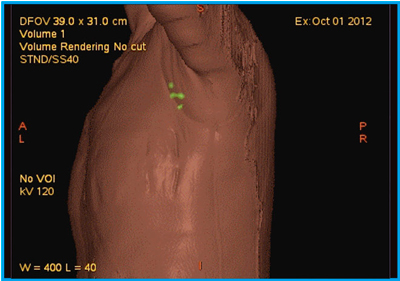

外科病理学 | 株式会社文光堂, MRエラストグラフィを導入しました<メディカルスキャニング千葉,

MRエラストグラフィを導入しました<メディカルスキャニング千葉, 医療法人 心葉消化器外科|トップページ,

医療法人 心葉消化器外科|トップページ, 進行性線維化を伴うCTD-ILD診療における急性増悪予防の重要性,

進行性線維化を伴うCTD-ILD診療における急性増悪予防の重要性, 論文紹介 | 滋賀医科大学 病理学講座 疾患制御病態学部門,

第52回日本核医学会学術総会/第32回日本核医学技術学会総会学術, 進行性線維化を伴うCTD-ILD診療における急性増悪予防の重要性,

進行性線維化を伴うCTD-ILD診療における急性増悪予防の重要性,